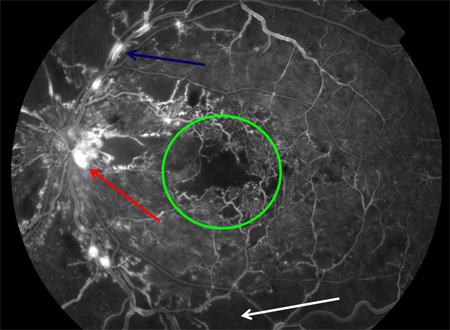

Fluorescein angiogram in proliferative diabetic retinopathy with macular ischaemia: macular ischaemia (green circle), capillary non-perfusion (white arrow), optic disc new vessels (red arrow), venous beading (blue arrow)

Courtesy of Moorfields Photographic Archive; used with permission